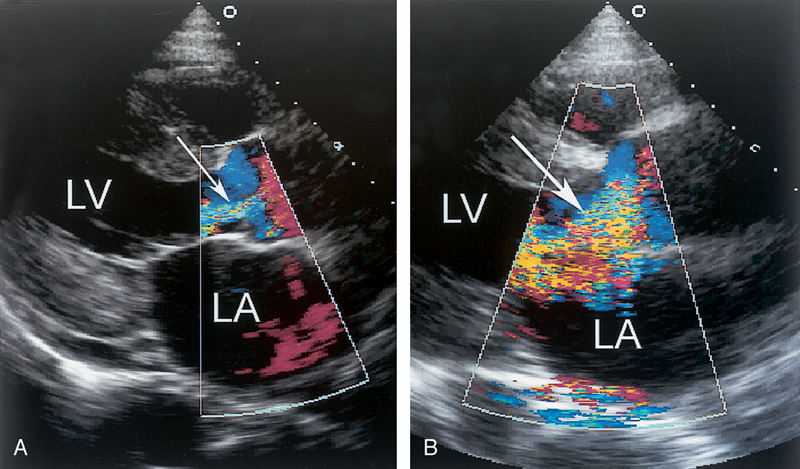

فحوصات تشخيصية لبعض امراض القلب والشرايين التاجية